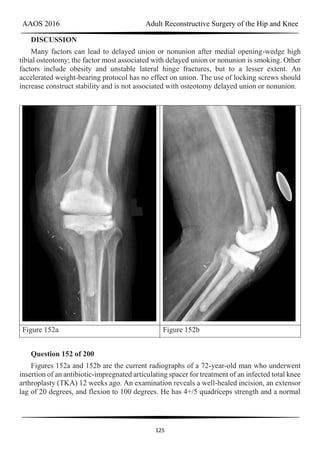

DISCUSSION

AAOS 2016 Adult Reconstructive Surgery of the Hip and Knee

18

Video 22 for reference

This patient has an unstable cruciate-retaining TKA. The tibial cut appears to be

substantial, necessitating a very thick polyethylene liner. In addition, the femoral component

may be slightly more proximally located. Tests for flexion-extension gap balancing would

indicate flexion instability. However, the possibility of infection remains, so screening blood

tests are appropriate. The surgical treatment for this unstable knee is revision TKA to a more

constrained implant, ensuring flexion-extension gap balancing. No evidence indicates that the

knee is infected. A thicker polyethylene insert will not adequately balance the knee.